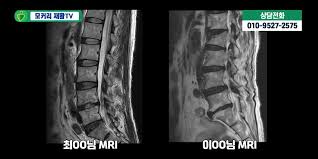

🩻 진단 방법

- MRI: 신경압박 정도, 협착 위치·범위 정확하게 파악